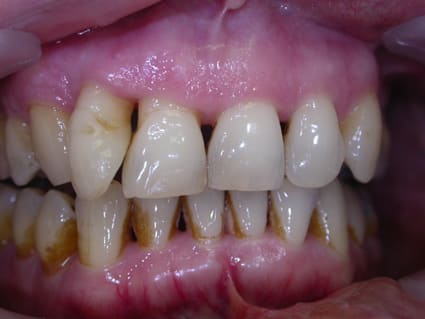

d'abord faudrait des photos ou des radios ..

la persistance de problèmes s'accompagne de quels signes ?

car il ne faut pas confondre la cause du problème qui est essentielllement à base infectieuse sur un terrain peut être prédisposé et la consequence du problème qui est la perte osseuse la presence de poches etc ... .....

si tu traites la cause tu gueriras l'infection mais il te restera peut être des sequelles ( pertes osseuses par exemple )

ensuite une fois seulement que l'infection sera maitrisée et seulement alors et si possible guérie alors seulement tu pourras penser à corriger les sequelles si une technique te le permet ce qui n'est pas toujours le cas ( alveolyse horizontale c'est pas evident ) ...

la correction si elle est possible pourra comporter des techniques de reparation ( allant du petit lambeau ) aux techniques de régénération ( par utilisation par ex des proteine dérivées de l'email ou autres membranes ..)

d'emblée si elle a eu curetage c'est une technique un peu dépassée et il est donc probable que l'on ne l'a pris en charge sur le plan de son infection au départ et des facteurs de risques evoqués par pierres....et que l'on a agit sur un terrain encore inflammatoire donc actif donc sans etre assuré d'une reponse naturelle initiale par traitements locaux peu invasifs et adaptés car lorsque l'on agit ainsi les curetages ne sont quasiment pas necessaires ( ce qui ne veut pas dire qu'une petite chirurgie ponctuelle n'est pas necessaire )